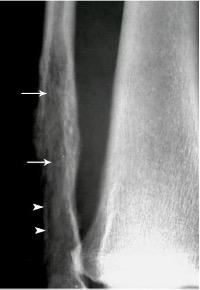

Ewing’s sarcoma

- Occur in immature skeleton

- Seen as an ill-defined, permeative lesion in diaphysis of a long bone or within a flat bone

- Often has cortical destruction and spiculated periosteal reaction

- Osteomyelitis has a similar radiographic appearance

Ewing’s sarcoma with ill-defined, permeative infiltration of fibula (arrows) and cortical destruction (arrowheads)